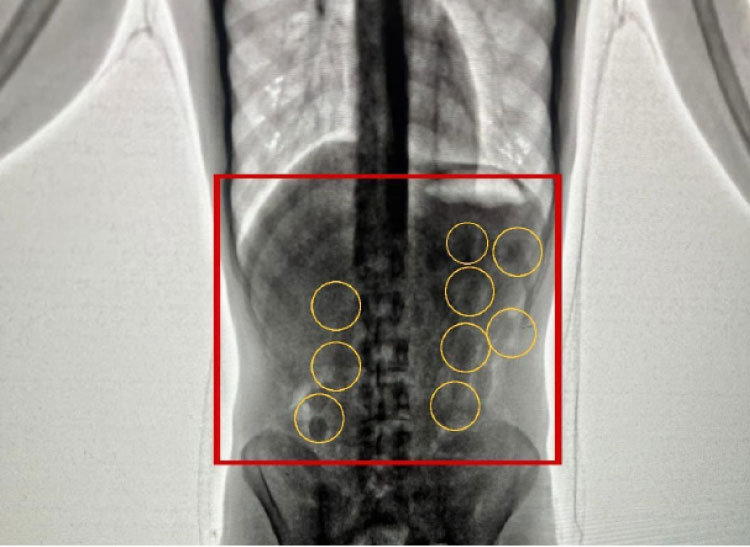

كشف الناطق باسم مديرية الامن العام في الأردن العقيد عامر السرطاوي ان إدارة مكافحة المخدرات أحبطت في مطار الملكة علياء الدولي، محاولة تهريب 2 كغم كوكائين، كانت في أحشاء شخصين من جنسية أجنبية، وذلك بعد متابعة معلومات، حول نية أجنبيين قادمين عبر المطار لتهريب مخدرات، خيث تم تحديد موعد وصول المشتبه بهما، وقبض عليهما فور محاولتهما دخول المملكة.وبعد تفتيشهما والكشف عليهما بواسطة الاجهزة، اكتُشف وجود مخدرات في أحشائهما، وجرى إخراج هذه المواد بطرق طبية، وقُدرت بـ2 كغم كوكائين.